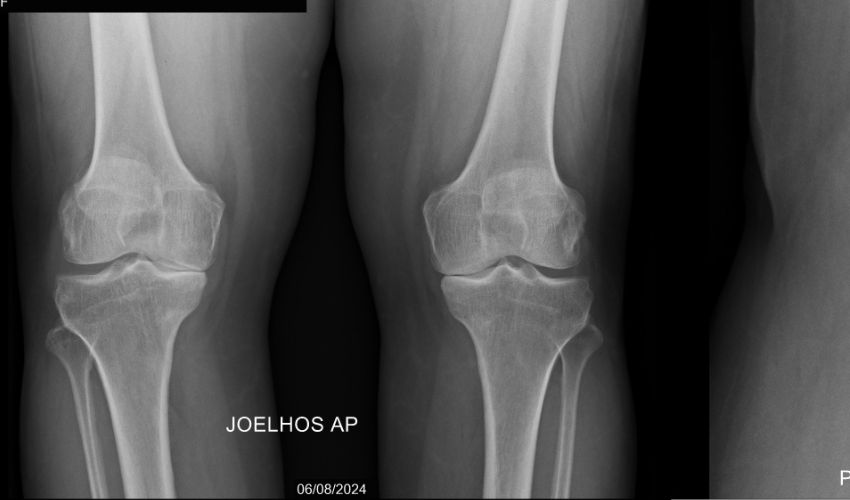

Maria de Fátima mora na zona rural de Triunfo, tem 46 anos e há cerca de 10 anos vem enfrentando artrose nos joelhos, que recentemente tem se agravado chegando a afetar o seu quadril

Ela é moradora do sítio Mulungu, município de Triunfo, no Sertão da Paraíba, tem 46 anos e há cerca de 10 anos vem enfrentando um problema de artrose nos joelhos.

Dona Maria conta que exames recentes constataram que a doença vem se agravando, apresentando pequenos cistos e derrames, além de já estar afetando seu quadril.

A dona de casa relata que sente muitas dores e que ao longo dos anos vem fazendo tratamentos com medicação e infiltrações no joelho. Mas, com o agravamento da doença, ela precisa colocar uma prótese total no joelho direito que custa R$ 16.500,00 à vista ou R$ 18 mil dividido em 5x.